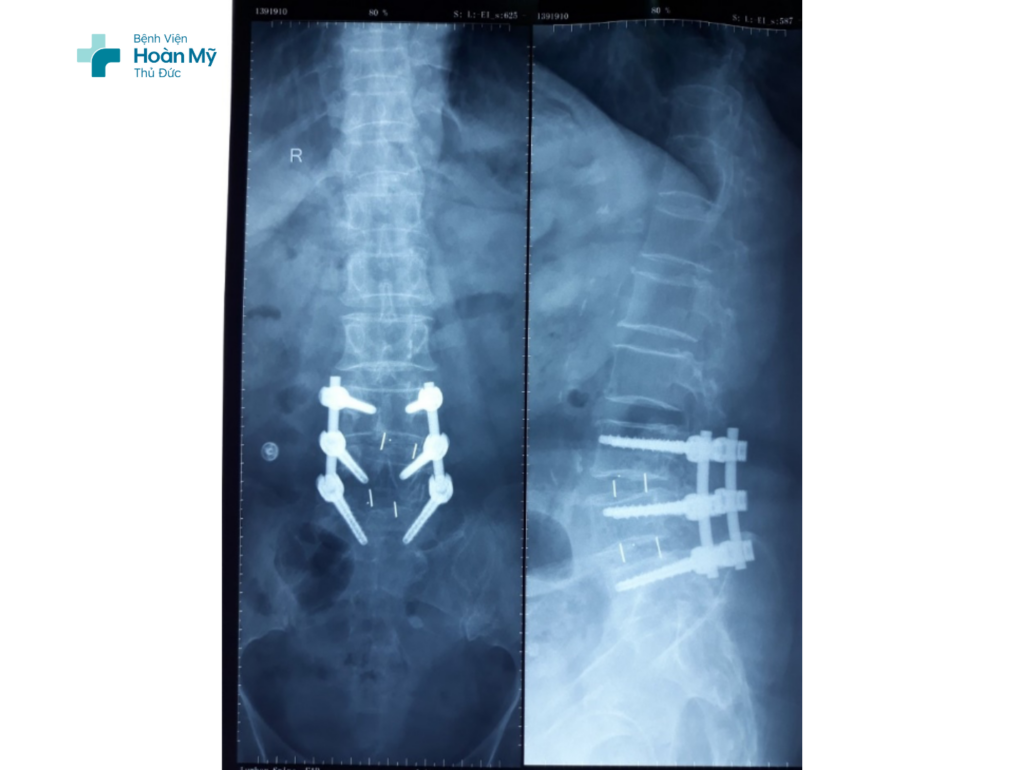

Hình ảnh phẫu thuật cố định cột sống bằng nẹp vít qua cuống lối sau

Sau khi được thăm khám lâm sàng tỉ mỉ kết hợp với kết quả cận lâm sàng – MRI cột sống thắt lưng, kết quả cho thấy “tầng L3-4 có tình trạng thoát vị đĩa đệm, hẹp lỗ liên hợp bên trái, chèn ép rễ thần kinh L3 trái; tầng L4-5 có lồi đĩa đệm, gây hẹp lỗ liên hợp hai bên, chèn ép rễ thần kinh L4 hai bên; thoái hóa đốt sống L3, L4, L5 kèm trượt L3-4, L4-5”. Bà T.L được chỉ định phẫu thuật cố định cột sống thắt lưng bằng nẹp vít qua cuống cung, ghép xương liên thất đốt qua lỗ liên hợp sử dụng hệ thống ống nong.

Cột sống thắt lưng của bà T.L đã được nẹp vít

Sau thời gian điều trị tích cực tại Bệnh viện và được theo dõi chặt chẽ trong phòng hậu phẫu 7 ngày, sức khỏe của bà T.L đã ổn định, biểu hiện chèn ép ống sống đã được giải quyết. Qua các lần tái khám, sức khoẻ bà T.L có tiến triển phục hồi rất tốt.